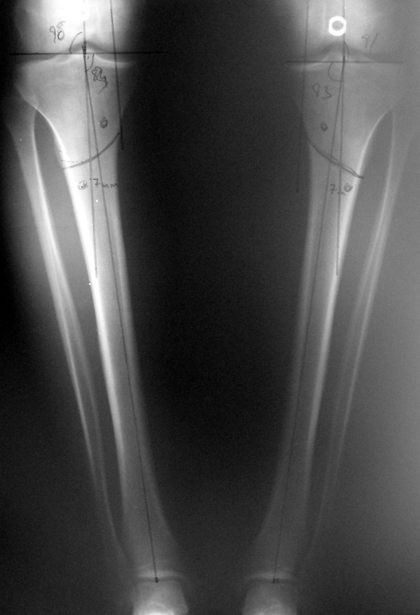

Lower limb length discrepancy is more than just a cosmetic problem; it leads to functional orthopedic problems. Orthopedic surgeons are very interested in the treatment of this pathological condition because imbalance at the frontal plane causes changes in walking pattern, and it also causes degenerative changes at the axial skeleton.

Today the most important properties that an extemity lengthening method shall possess are application time, ability to correct alignment (anatomic and mechanical axis of the extremity), number of total operations required, ability to protect the regenerated bone from refracture, minimum rate of pin tract site infection and possible complications, preservation of joint motion, healing time, comfortability in daily life and application cost.

Despite low sample size, our aim was to compare two groups with matching ethiology, age, location and amount of the deformity and other similar factors. We neglected simultaneous tibial lengthening and osteotomy site in this preliminary study. The sample size was not enough to conduct a prospective randomized trial. Although the results of the study did not produce statistically significant data, it is the first and only example in our country and conveys significant experience.